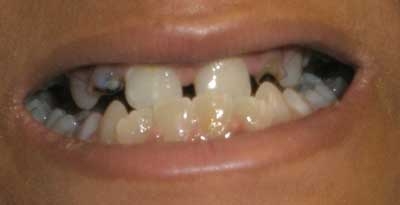

This patient has osteogenesis imperfecta (OI), an autosomal dominant connective tissue disorder commonly caused by a type I collagen mutation. Type I collagen is a critical structural component of tissues in the bone, sclerae, skin, and teeth. OI has a varying spectrum of severity, from mild (type I) to lethal (type II) disease.

Due to defective collagen in osteoid (extracellular bone matrix), patients often begin having frequent fractures from minor trauma once they become mobile (around age 1). Many patients with OI also have dentinogenesis imperfecta, an opalescent blue-gray or yellow-brown discoloration of the teeth caused by discolored dentin shining through translucent and weak enamel. Joints are often hypermobile due to ligamentous laxity. Scleral thinning can lead to the appearance of blue sclerae; other manifestations depend on the severity of the disorder and may include hearing loss and short stature.